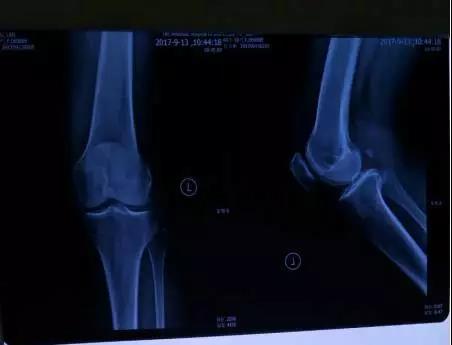

在家人的陪伴下,陳阿姨去暨南大學(xué)附屬第一醫(yī)院做檢查顯示: 1.膝關(guān)節(jié)輕度退行性改變;2.外側(cè)半月板前角及內(nèi)側(cè)半月板后角變性;3.髕上滑膜囊及關(guān)節(jié)囊少量積液。醫(yī)生開了些消炎止痛的藥物,治療效果不明顯,后來自己又找朋友開了些中藥,也是效果甚微。如此反復(fù),折騰了一個(gè)月,膝關(guān)節(jié)疼痛始終沒有得到改善。后來在朋友的介紹下,來到暨南大學(xué)“三得技術(shù)”治療室。開始接受“三得技術(shù)”治療。